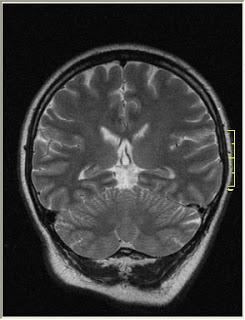

Gliome cérébral de bas grade.

Source: https://commons.wikimedia.org/wiki/File:Brain_MRI_glioma_077.jpg